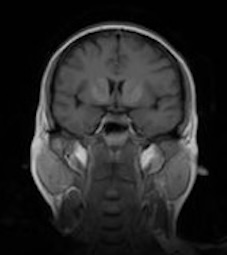

The Brain Tumor MRI Images dataset is a publicly available dataset on Kaggle555https://www.kaggle.com/datasets/sartajbhuvaji/brain-tumor-classification-mri/data. It contains MRI images of human brains divided into four categories: No Tumor, Pituitary Tumor, Benign Tumor, and Malignant Tumor. For our study, we selected three categories: No Tumor (NT), Benign Tumor (BT), and Malignant Tumor (MT). From each category, we chose three MRI images representing different parts of the brain that best illustrate the characteristics of each class. The categories included in this study are described as follows:

Figure 5. Axial and Coronal MRI Images of Brains Representing Different Tumor Categories

Differentiating these categories is essential for early detection, accurate diagnosis, and effective treatment planning. By distinguishing between healthy brains, benign tumors, and malignant tumors, medical professionals can identify abnormalities more reliably, reduce misdiagnoses, and streamline medical care. In this study, we apply our divergence measure to differentiate between the selected MRI images, as illustrated in Figure 5. In Figure 5, the first row shows MRI images from NT patients, the second row shows images from BT patients, and the third row shows images from MT patients.

Using the divergence measure, we calculated estimates for each pair of MRI images and compared the three categories. For calculation, each grayscale image is represented by its pixel intensity values (scaled to [0,1]). These values are flattened into a one dimensional vector and used as the sample data for subsequent analysis. For any two images, denoted data1 and data2, we then computed an empirical based divergence estimate. The resulting values are presented in Tables 4, 5, and 6. A higher value of the divergence estimate indicates a greater likelihood of a tumor. These results demonstrate that the divergence measure can serve as an effective tool for detecting tumors in medical image data.

Table 6. Estimated Divergence Measure Values for Pairs of Different Classes in Coronal View Brain MRIs

NT2 BT2 MT2

NT2 0 0.023 0.032

B2 0.023 0 0.023

MT2 0.032 0.023 0